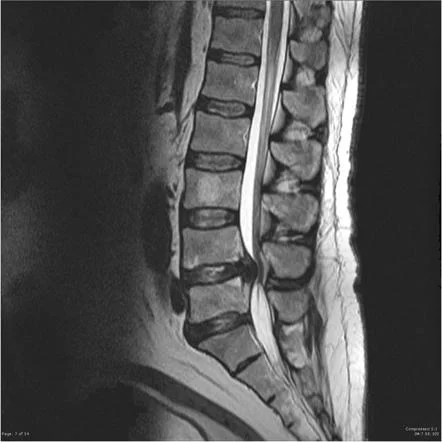

- MRI:最も確定診断に有用ではありますが、診察との整合性が大事です。

- MRIで観察すると飛び出したヘルニアが縮小・消失することは非常に多い。

MRI(非常に重要)

- 新しい圧迫骨折かどうかが明確に分かる

- 骨の中の浮腫(むくみ)が明るく写る

- 多発の確認がしやすい

脊柱管狭窄症は脊髄や神経根が通る「脊柱管」が狭くなり、神経が圧迫されて起きる症状の総称です。原因は加齢による椎間板の変性、椎間関節(ファセット)の肥厚、靭帯(黄色靭帯)の肥厚、骨棘などの変化が主です。先天的に狭いタイプもあります。画像(MRI)で脊柱管の狭小化が確認できますが、画像で狭いところがある=必ず症状が出るとは限りません(臨床所見との照合が重要です)。

- 画像検査:レントゲンとMRIが最も有用。CTを追加することもあります。しかし重要なことは、これらの画像検査は診断の参考程度のものであり、治療方法の判断は総合評価にて行います。